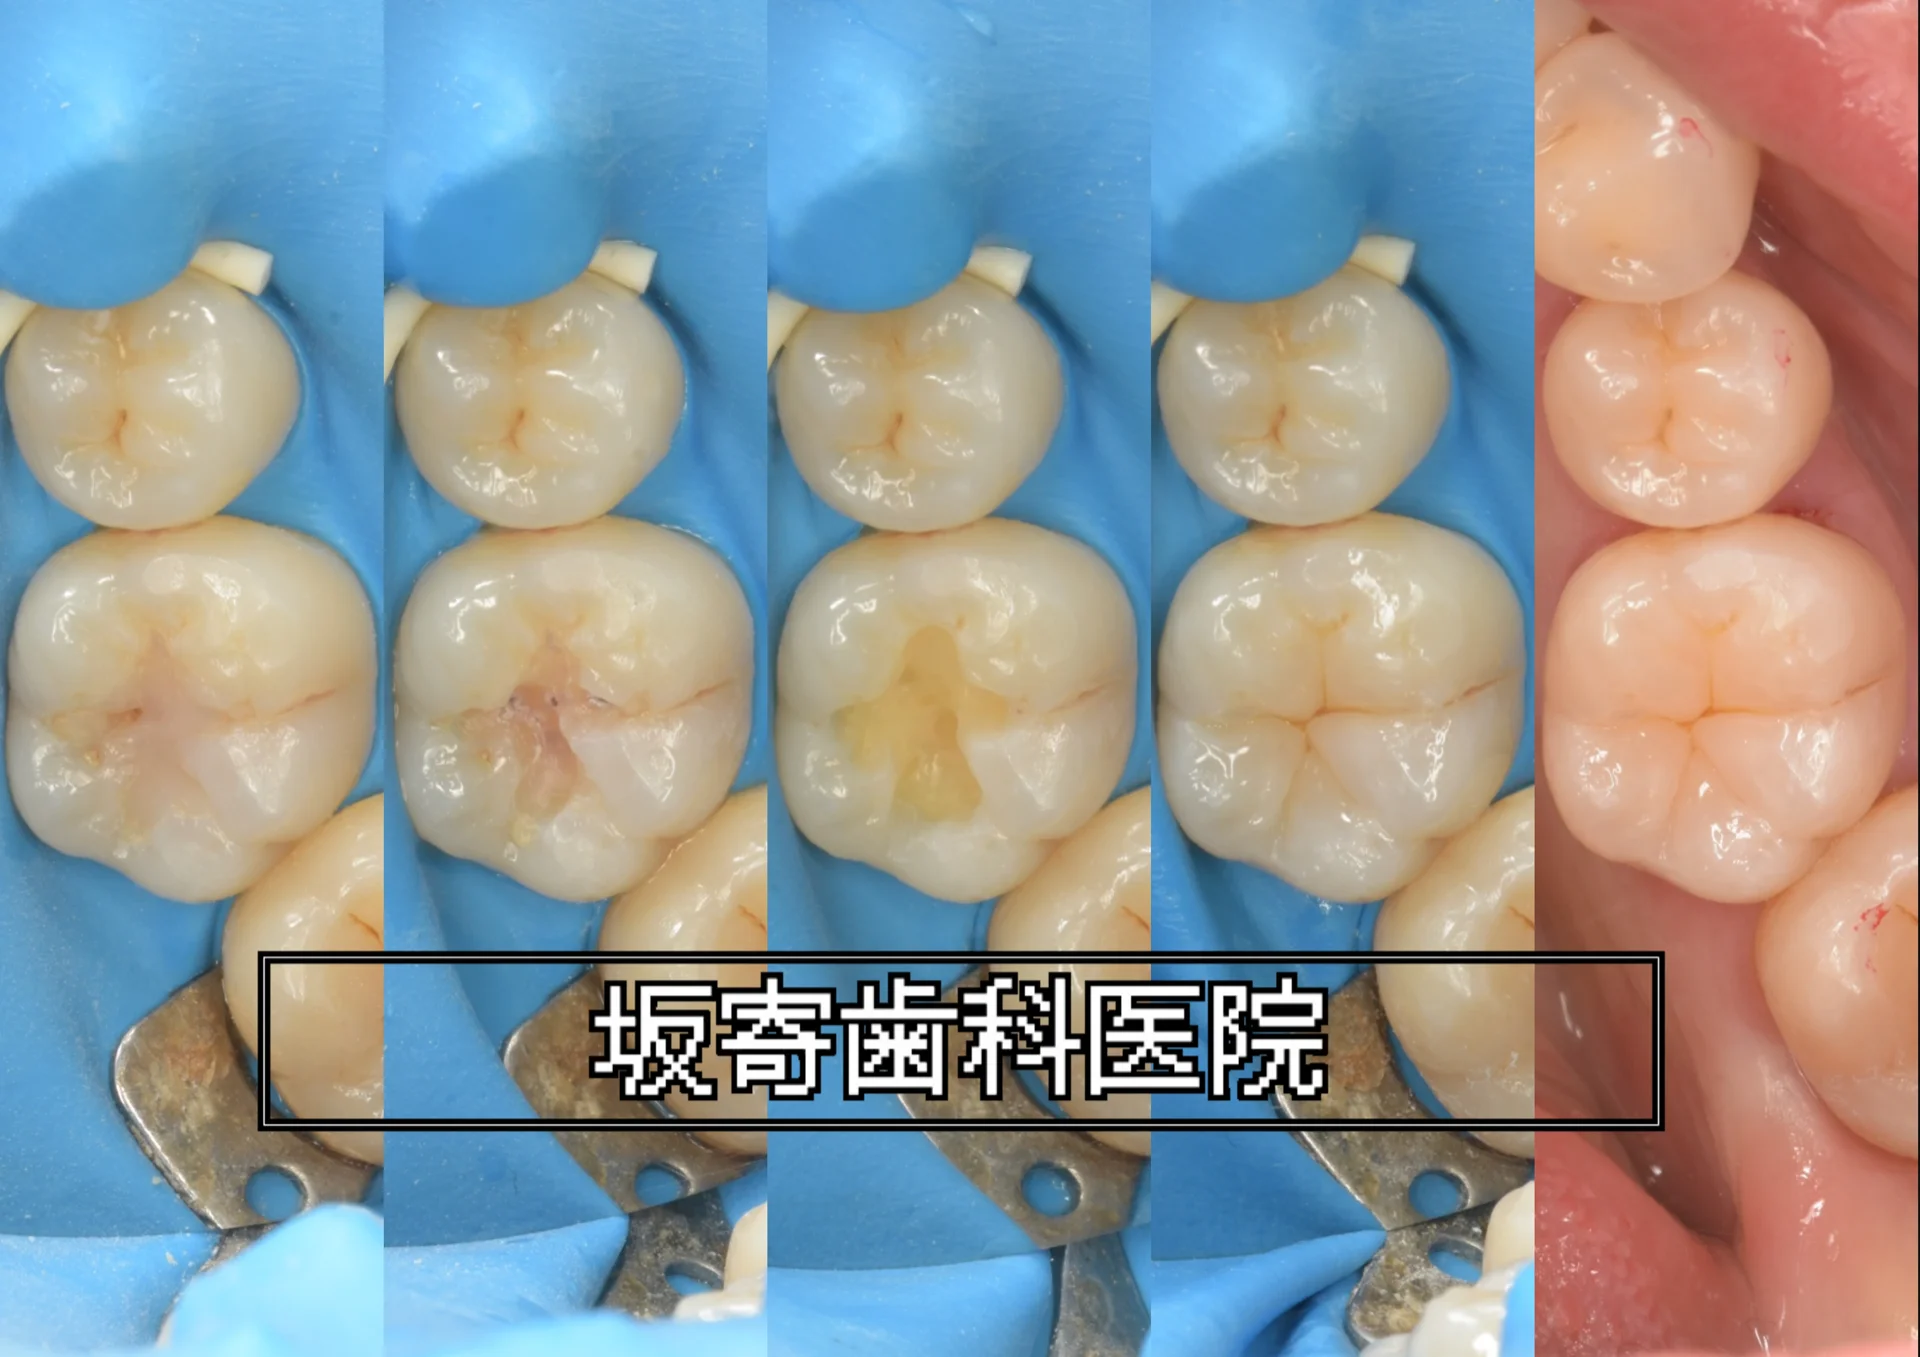

歯質を温存しながら左上の臼歯3本をダイレクトボンディングで修復

東京都内からお越しの30代女性(歯科医師)の患者さんです。経過観察していた左上5番 近心のむし歯が象牙質の半ば(1/2程度)まで進行したため、左上4・5・6番の3本を同日にダイレクトボンディングで修復した症例です。健康な歯質を最大限温存することを優先し、ラバーダム防湿下で精密に接着処理を行いました。

近心クラックから生じた二次う蝕をダイレクトボンディングで修復

東京都新宿区からお越しの40代女性の患者さんです。右上7番 近心のクラック(ひび)を起点に、以前に入っていたインレー(部分的な詰め物)の下でリーケージ(漏洩)が進み、二次う蝕・感染に至っていた症例です。隣接面の接触がしっかりしておりラバーダムが入りにくい条件でしたが、排唾管による防湿で接着環境を確保し、ダイレクトボンディングで修復しました。